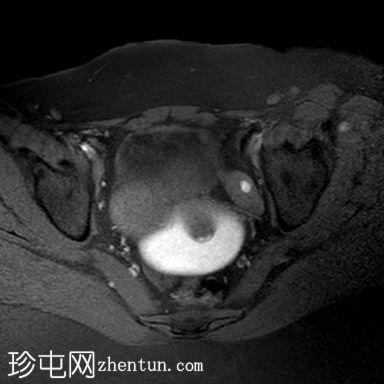

轴位 T1加权像

脂肪抑制序列

阴道明显扩张,T1加权像呈中高信号,T2加权像呈高信号,耻骨联合下方可见一小局灶性隆起。

右侧卵巢可见一圆形、边界清晰的囊肿,最大轴位径为4.2 x 4.3 cm,T1加权像呈低信号,T2加权像呈高信号。

左侧卵巢大小正常,可见一小出血性囊肿。